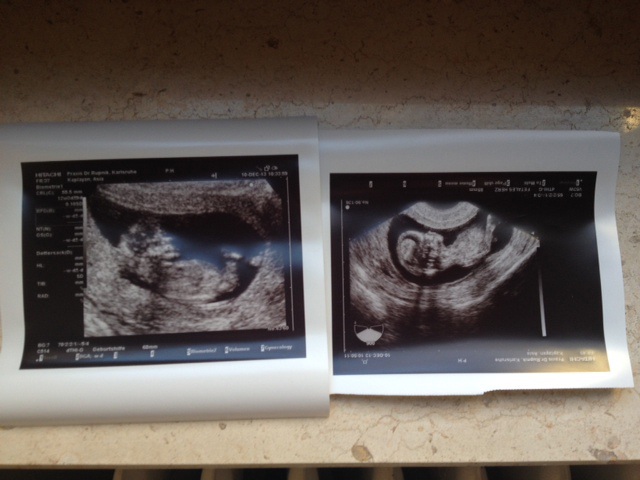

Сходили мы на УЗИ первого триместра. Ходила с мужем, ему очень понравилось! Малыш так там кувыркался и пинался. КТР - 55.5 мм, голова - 22 мм, воротниковая зона - 1.1 мм. Еще взяли анализы крови, сказали, позже будут результаты. Вес мой стоит на месте - 48 кг, ни на грамм не изменился, хотя джинсы жмут уже немного.

Так вот, на главный вопрос - кто в домике, врач так и не ответил :( Сказал, что не будет гадать. А мне интересно - аж жуть. Видно вам что-нибудь, девоньки? :)